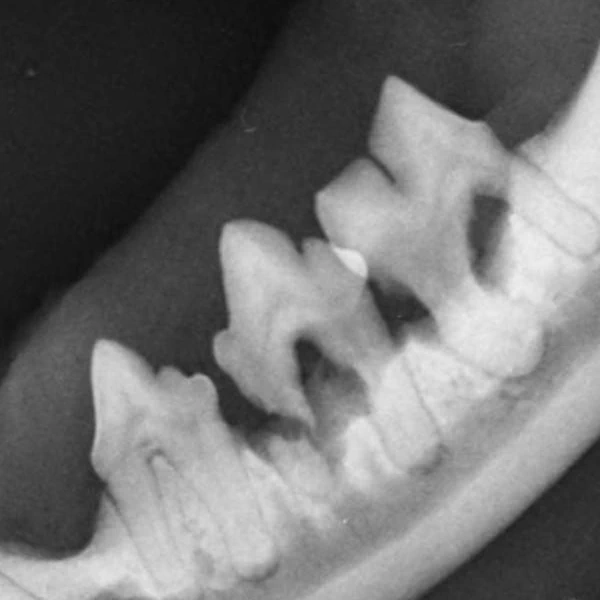

Röntgen

In unserer Praxis halten wir ein modernes digitales Röntgensystem bereit. Dieses wird regelmäßig vom TÜV geprüft. Bitte haben Sie Verständnis, dass Sie nicht beim Röntgen dabei sein können.

Normalerweise röntgen wir unsere Patienten ohne Sedierung. Sollte Ihr Tier jedoch sehr ängstlich oder sehr unkooperativ sein, kann es erforderlich sein, eine kurze Sedierung einzuleiten. Nur so können fachlich korrekte und aussagekräftige Röntgen-Aufnahmen erstellt werden.

Bei Zuchtuntersuchungen auf HD (Hüftgelenksdysplasie) als auch ED (Ellenbogengelenksdysplasie) ist eine muskelerschlaffende Kurznarkose unabdingbar und durch die Zuchtverbände i.d.R. vorgeschrieben.

Die Röntgenbilder stehen innerhalb weniger Minuten zur Beurteilung zur Verfügung.